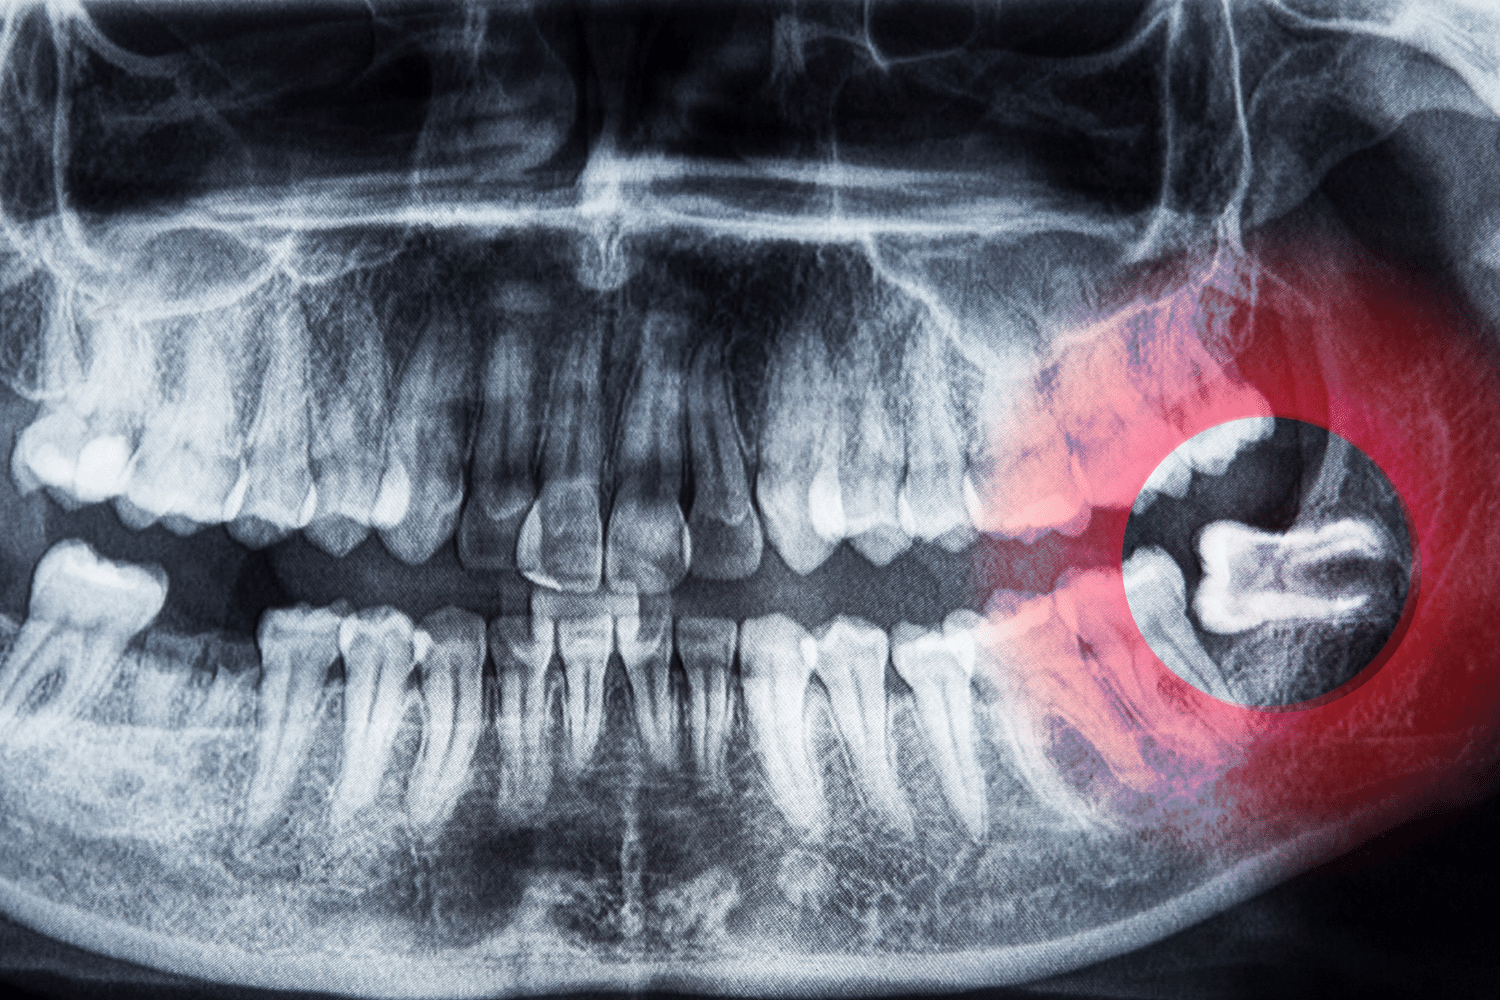

Impacted Wisdom Tooth Extraction

Impacted wisdom tooth extraction is a surgical procedure to remove wisdom teeth that have not fully erupted. These teeth can cause pain or infections. Our skilled practitioners use advanced techniques to safely and effectively address the issue, prioritizing your comfort and recovery.

An Impacted Tooth

When a tooth cannot emerge properly, causing pain and misalignment, extraction can relieve discomfort and correct alignment.